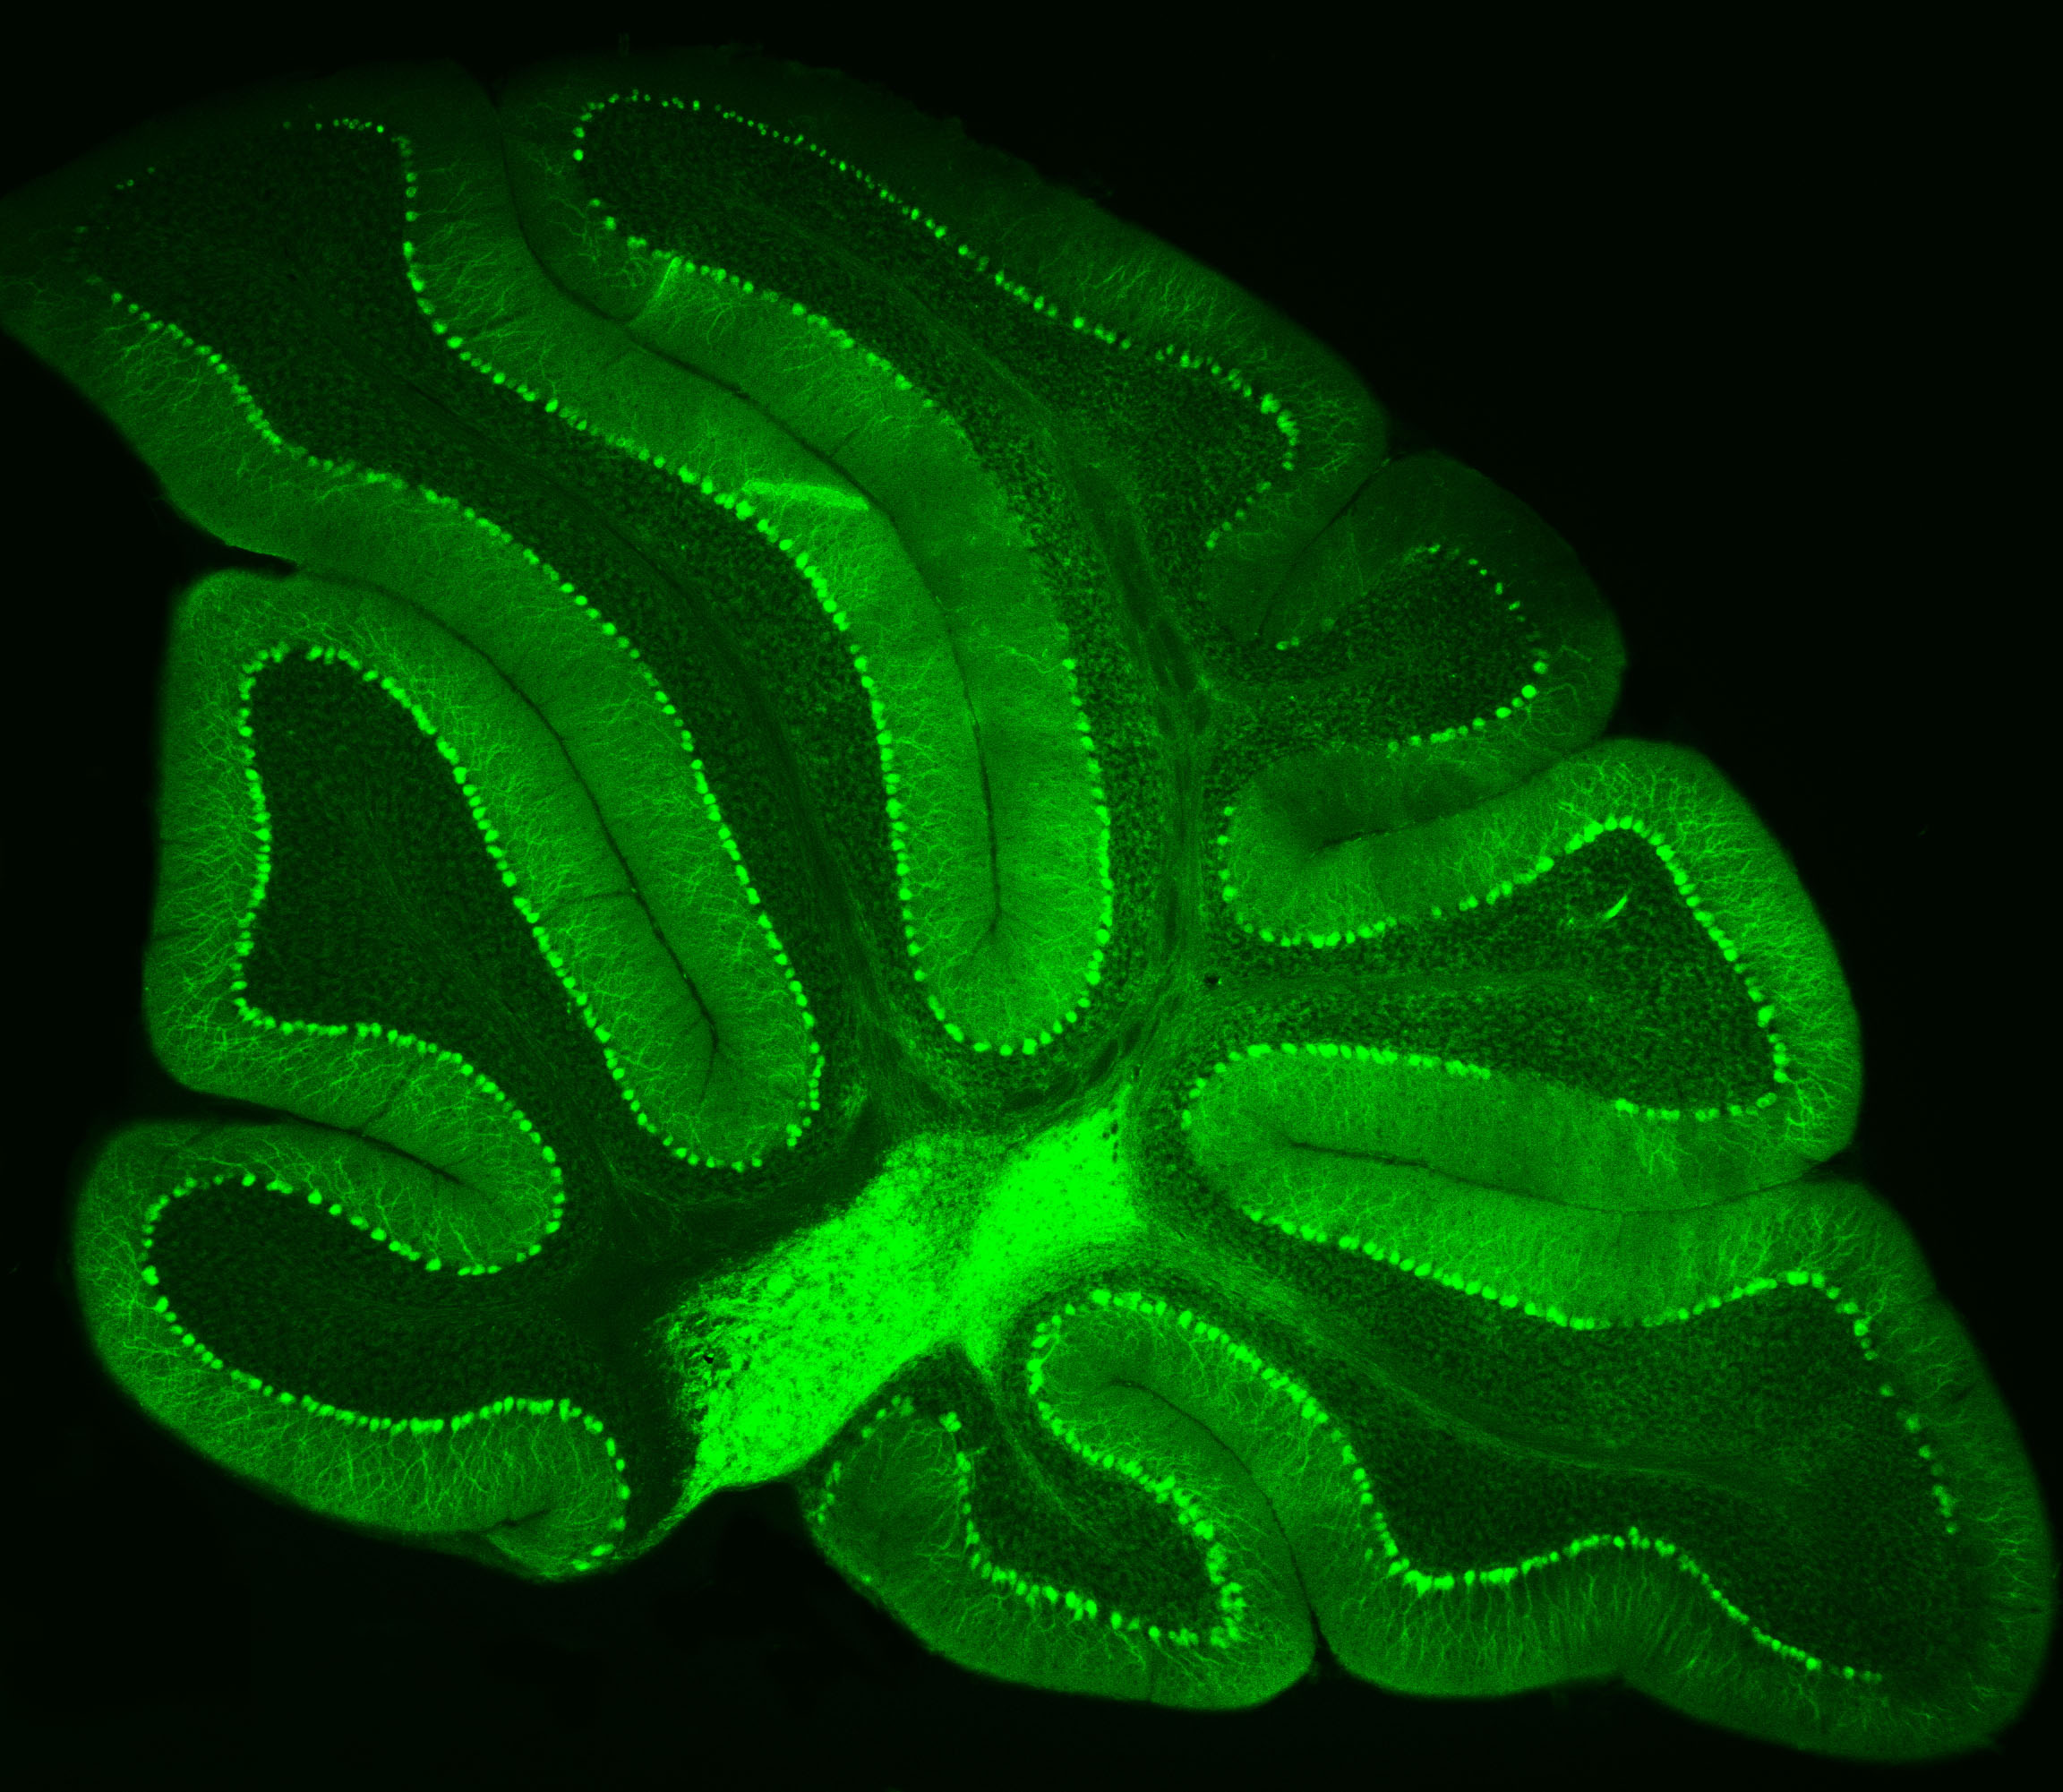

Neurons in Green

Purkinje neurons from an animal model are labeled with green fluorescent protein (GFP), which causes them to glow bright green. Credit: Pennington Biomedical

Purkinje neurons from an animal model are labeled with green fluorescent protein (GFP), which causes them to glow bright green.

– Credit: Pennington Biomedical

At Pennington Biomedical Research Center, scientists often study the brain by highlighting specific cells so they can be seen more clearly under a microscope. This technique was recently used by Dr. Yanlin He, associate professor and director of the Brain Glycemic and Metabolism Control Laboratory, who is examining Purkinje neurons in the cerebellum.

Purkinje neurons are best known for helping control movement and motor learning, but researchers are discovering they may have other important roles in the body as well, such as controlling energy balance and blood sugar.

By making these neurons glow green, Dr. He and his team can see their complex branching shapes and how they connect within the cerebellum’s neural network.

This technique also allows researchers to perform electrophysiology recordings, which measure the electrical activity of the cells in a laboratory setting. Their work could help scientists better understand how the brain helps regulate metabolism and overall health.